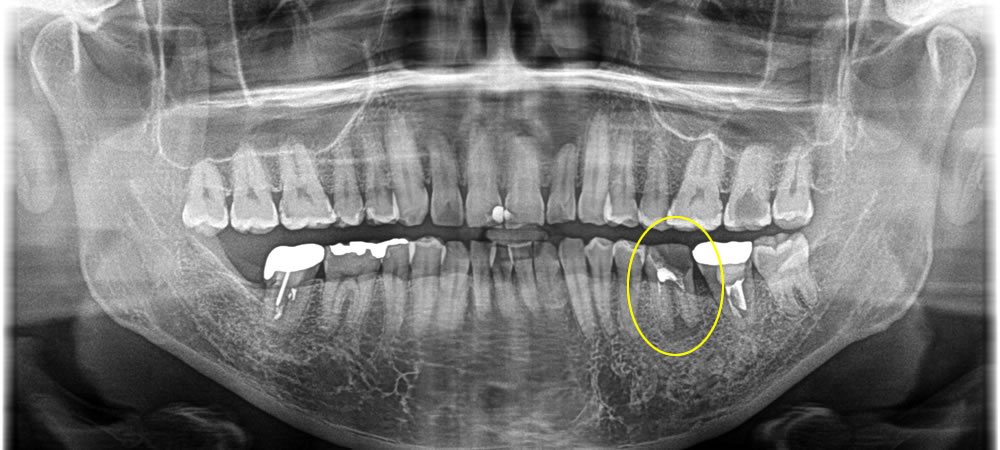

歯根に膿が溜まった歯を抜歯してインプラントで治療した症例

年齢

30代

性別

女性

症例を見る